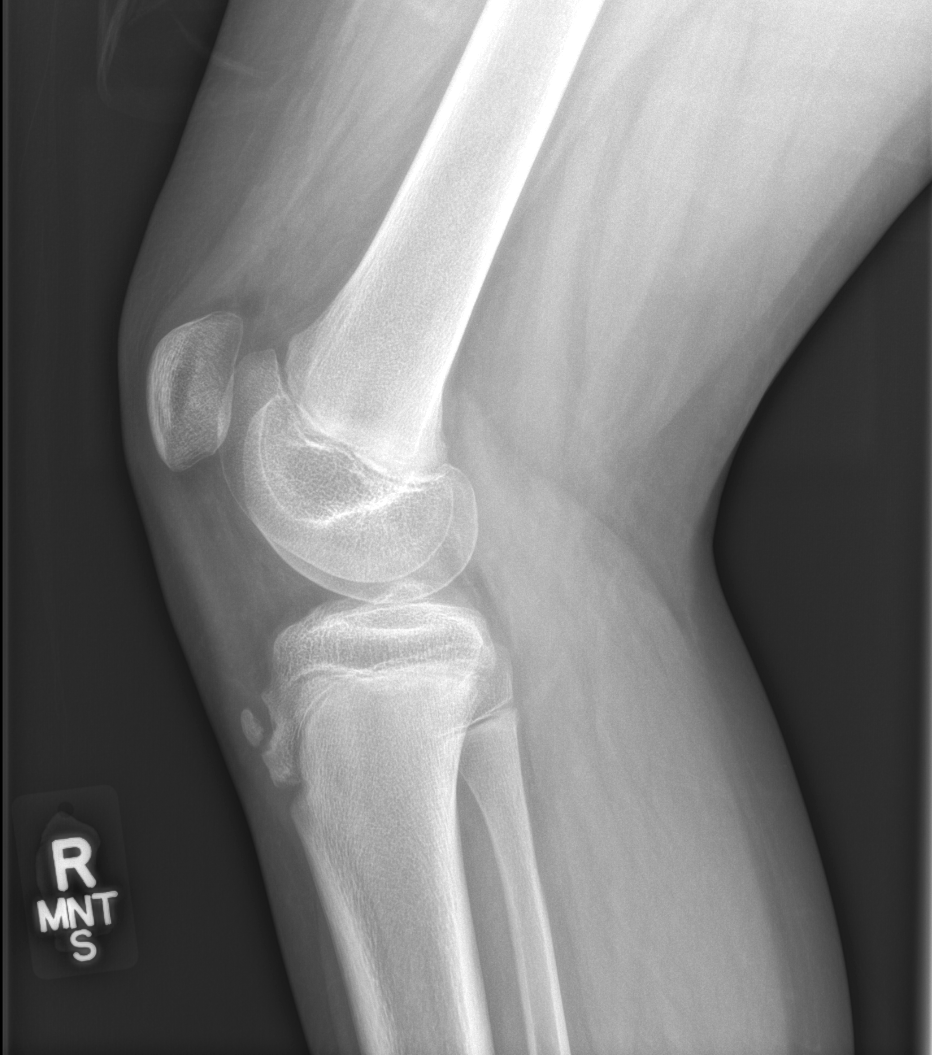

Section 1 Submit Findings CB1550 Findings Skeletal Survey - Technique Check Skull AP/Lat Yes No Cervical and Thoracolumbar spine Yes No Chest X-Ray Yes No Ribs – Left/Right Oblique Yes No Abdominal X-Ray Yes No Pelvis with both hips Yes No Bilateral Humerus, Forearm, Hand Yes No Bilateral Femur, Tibia/fibula, feet Yes No Any additional lateral views of the extremities Yes No The exam is over or under penetrated. Yes No The exam may or may not be limited by overlying structures or soft tissues, body habitus, patient positioning, support devices, or motion. Yes No The area of concern is indicated by the patient, technologist, or care provider. Yes No The area of concern is included on the exam. Yes No Soft Tissues There is soft tissue swelling, indistinctness of fat/muscle planes, gas, or laceration in the area of clinical concern. Yes No There is an effusion, fat pad displacement, or fat fluid level. Yes No There is a radiodense or lucent foreign body. Yes No There are other densities, calcifications, post-surgical changes, or support devices in the soft tissues. Yes No Any support lines/tubes. Yes No Bone There is a break or interruption of the continuity of the cortical or cancellous bone. Yes No There is overriding of the trabeculae with apparent sclerosis. Yes No There is displacement of a fracture fragment. Yes No There is bowing of the bone in addition to the fracture at the apex of the bowed bone concerning for the greenstick. Yes No There is a spiral fracture of the leg concerning for toddler’s fracture. Yes No There is abnormal angulation or bulging of the cortical surface relative to the normal cortex which could be from a buckle or torus fracture. Yes No There is a displaced fragment which may be from avulsion by a tendon, ligament, or joint capsule or from a comminuted or other fracture. Yes No The stress trabeculae or other trabeculae of the cancellous bone are interrupted or otherwise abnormal. Yes No There is subperiosteal or endosteal reaction which could indicate a healing or subacute fracture or other abnormality. Yes No There is hard/soft callus formation. Yes No There is remodeling of the bone. Yes No There is a corner fracture or metaphyseal lesion that could be from nonaccidental trauma. Yes No There are multiple fractures of different ages. Yes No There are vertebral body/spinous process fractures. Yes No There are rib fractures. Location - posterior or lateral. Yes No There is scapular/sternal fracture. Yes No There are fractures of the digits. Yes No There are wormian bones. Yes No There are intrasutural bones. Yes No There is metaphyseal abnormality (lucencies, increased density, erosion) which may be from something other than injury such as stress, metabolic disease (e.g. rickets with loss or distortion of the zone of the provisional calcification), neoplasm (e.g. leukemia), heavy metals, inflammation, or infection. Yes No There are metaphyseal spurs. Yes No There are bony deformities involving multiple bones. Yes No The bones are gracile. Yes No There are non-healing fractures. Yes No There is/are focal or multifocal lytic/lucent, blastic/sclerotic or mixed density lesion(s) or other abnormality. Yes No Overall bone density is increased or decreased with or without thinning or thickening of the cortical or cancellous bone. Yes No Growth plates, ossification centers, apophyses The growth plate(s) is/are abnormal. Yes No There is widening of the physis from a fracture with or without displacement of the epiphysis (Salter-Harris I). Yes No There is a fracture through the physis which then extends into the metaphysis with or without angulation or displacement (S-H II). Yes No There is a fracture through the physis which then extends into the epiphysis and is intra-articular, with or without angulation or displacement (S-H III). Yes No There is a fracture through the metaphysis, physis, and epiphysis which extends into the joint space with or without angulation or displacement (S-H IV). Yes No There is narrowing of the physis from a compression fracture (S-H V). Yes No The apophysis, epicondyle, secondary ossification center, or accessory ossicle is displaced or otherwise abnormal. Yes No The ossification centers are underdeveloped. Yes No Joints and alignment There is an effusion, fat pad displacement, or fat fluid level. Yes No The epiphysis or subchondral bone is fractured, interrupted, flattened, compressed, impacted, displaced, or otherwise abnormal. Yes No There is an intra-articular loose body or chondrocalcinosis. Yes No The joint is widened, narrowed, dislocated, malaligned, or incongruent. Yes No There is pseudoarthrosis. Yes No Other findings There are developmental changes or other anatomic variants or other existing conditions that may or may not be contributing to symptoms which can or should be further evaluated non-emergently or are otherwise incidental. Yes No The remainder of the exam is abnormal for age. Yes No The lungs show focal airspace opacity. Yes No There is pneumothorax. Yes No There is organomegaly. Yes No There is intra-abdominal calcification. Yes No There is displacement of the bowel loops. Yes No There is free intraperitoneal air. Yes No The bowel loops are dilated/obstructed. Yes No There is paraspinal soft tissue abnormality. Yes No